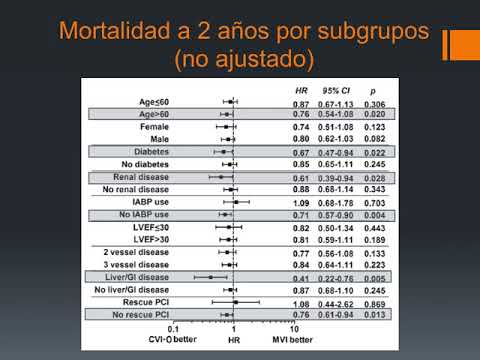

Revascularización de vaso culpable vs múltiples vasos. Dr. Pablo Rivara. Residencia de Cardiología. Hospital C. Argerich. Buenos Aires